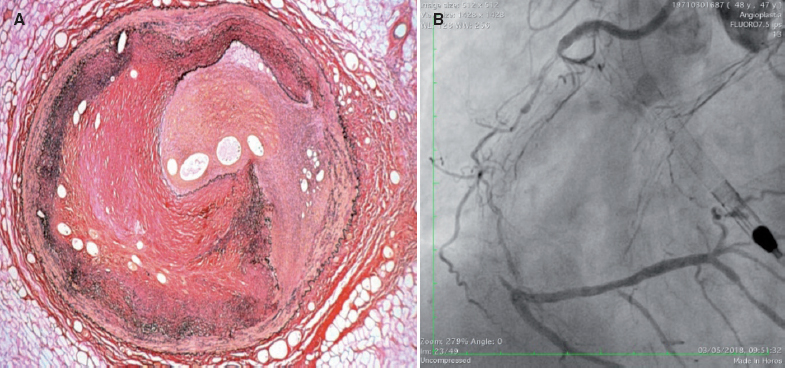

An important aspect is the process of neovascularization that happens all through the occlusive lesion and on the vessel wall. Neoangiogenesis grows with the time of occlusion. In CTO durations < 1 year, the formation of new blood capillaries is predominantly adventitial. In CTO durations > 1 year, there is usually a rich network of new blood vessels running through the adventitial layer of the vessel wall towards the intima forming the bridging collaterals. The process of new vascular formation can promote the formation of relatively long capillary blood vessels called microchannels that run through the body of the occlusion partially recanalizing the distal lumen (figure 1A). Their presence is important because an angioplasty guidewire with hydrophilic coating can run through them and reach the distal lumen. Also, microchannels can connect to the vasa vasorum of the adventitial layer creating an extraluminal collateral pathway to the distal lumen with the typical appearance of caput medusae (figure 1B). This is typical of complex CTOs of long duration. In general, the toughness and density of the fibrocalcific material and the complexity of the CTO are related to the duration of the occlusion.2

Figure 1. A: presence of microchannels inside the vessel lumen surrounded by significant fibrosis. B: typical caput medusae extraluminal neovascularization.